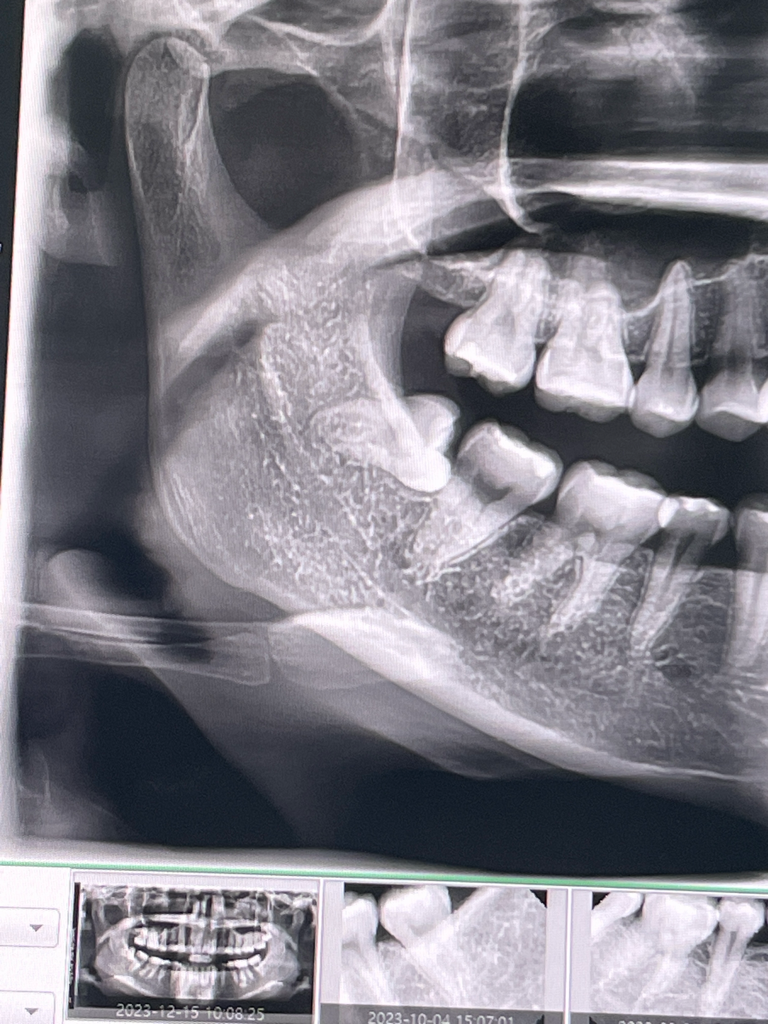

매복사랑니 발치 3일차 온찜질 냉찜질? 통증? 염증?

매복사랑니 발치는 11월 15일 오전 11시에 했어요

엑스레이사진대로 조금 어려운 수술이라고 하셨습니다.

• 1번 째 사진